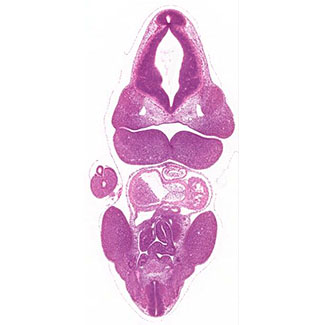

a histology section of a human embryo   a histology section of a mouse embryo

a histology section of a human embryo